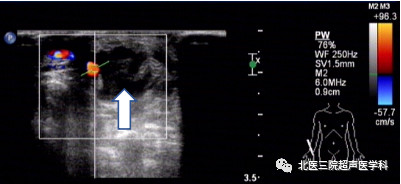

52岁男患,左前臂造瘘术后8年,触诊瘘口震颤减弱。超声证实头静脉近瘘口处严重狭窄